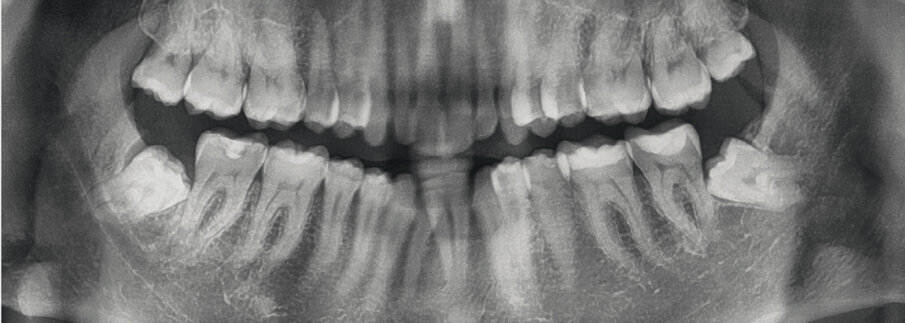

Dal punto di vista parodontale il paziente ha mostrato una buona attitudine all’igiene orale, ma l’affollamento degli incisivi mandibolari ha reso difficile la pulizia in quell’area, causando un accumulo di placca e un’infiammazione gengivale localizzata. La radiografia panoramica ha rivelato la presenza dei terzi molari mandibolari e ha confermato l’assenza dell’incisivo centrale mandibolare destro (Fig. 10). L’analisi cefalometrica ha evidenziato una malocclusione scheletrica di Classe II (convessità del Punto A: 4,9 mm), una posizione leggermente retrusa del mento (profondità facciale: 78,1°) e una tendenza scheletrica al morso aperto (altezza facciale inferiore: 53,19°; asse facciale: 80,58°; Fig. 9). Gli incisivi mandibolari erano inclinati lingualmente (Li-APog: 9,3°) e retrusi (Li-APog: 1,55 mm), con un angolo interincisivo aumentato di 142,9°.